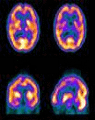

Dentro de este campo científico apasionante existe un debate sobre en qué momento el ser humano tiene un cerebro funcional. Las posturas difieren de formas agresivas porque entran grandes en cuestión temas éticos como el aborto o la eutanasia. ¿Cuándo nace el cerebro?,  ¿cuándo se produce la muerte cerebral?

Para los científicos, a las 26 semanas de gestación, el cerebro ya está empezando a desarrollarse y puede sentir dolor psicológico. "Lo único que se puede decir con certeza es que a los 14 días en el embrión no hay cerebro, y éste es un dato importante, porque los científicos que investigan con células madre en medicina regenerativa utilizan células embrionarias de menos de 14 días". Eso podría arrojar luz y límites a este debate.

Se admite la muerte cerebral cuando no hay actividad en el cerebro y se acepta la muerte cerebral para poder extraer los órganos de un cuerpo humano. Del mismo modo ¿se podrían utilizar o donar a la medicina organismos que no tienen cerebro? En esta cuestión, algunos apelan a la potencialidad, es decir, a que ese embrión podría llegar a tener un cerebro. No es sencillo llegar a acuerdos.

La muerte cerebral se inicia en la corteza, rápidamente afecta a todo el cerebro y termina siendo una muerte de todo el cuerpo. Son los neurólogos quienes determinan el momento en el que el cerebro ya no funciona y es un estado irreversible, final. En un estado vegetativo, sin embargo, los neurólogos no saben si dicho proceso es irreversible, pues se han dado casos de enfermos que despiertan de ese estado. El debate está en que algunos rechazan declarar la muerte mientras siga latiendo el corazón y pretenden revisar el concepto de muerte cerebral.